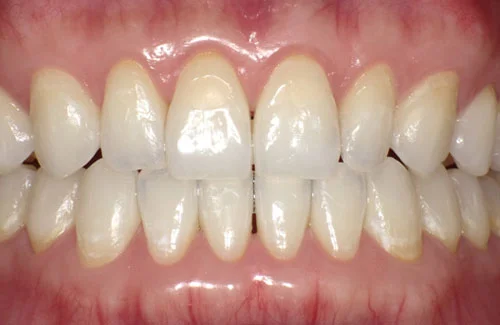

治療前後の写真

<症例2>歯が全体的にガタガタ、出っ歯でお悩み

歯列のアーチがやや狭く、それにより上下の前歯部にガタつきが生じている状態でした。

小臼歯部をわずかに広げてスペースを作ることで、お口元を整えつつガタつきを改善しています。

患者様と症状

主訴:全体的なガタガタ、出っ歯

性別・年齢:30代女性

問題点:上下前歯部の叢生(中程度)、ディープバイト

診断:前歯部の叢生を伴うアングルⅠ級の不正咬合

主なリスク:矯正中一時的に咬合しにくくなる、歯肉退縮

症状:叢生(そうせい) 過蓋咬合(かがいこうごう)

治療内容

治療期間:9ヶ月

治療費用:660,000円(税込)

プラン:26枚コース/モデレートプラン

抜歯:親知らずのみ抜歯

再診治療費:無し

追加治療費:無し

保定装置費:無し